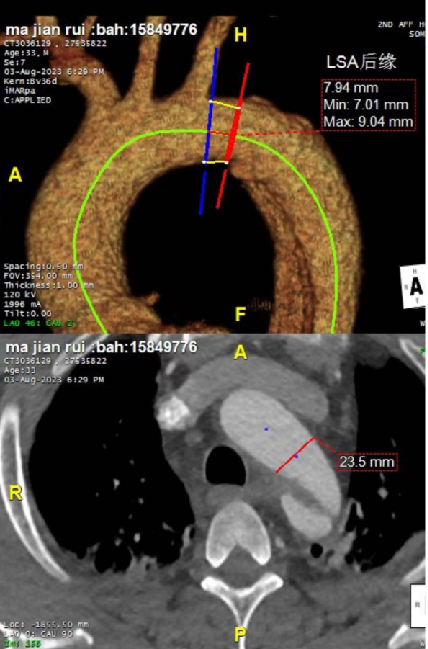

患者很年轻,不希望支架开窗或干扰左锁骨下动脉,但破口紧邻左锁骨下动脉小弯侧(小弯侧破口距锁骨下动脉只有7mm,大弯侧9mm),挑战比较大。需要评估是否延长近端锚定区以覆盖病变,同时避免影响重要分支血供。

② 多破口处理:针对四处破口的复杂性,需平衡完全封堵与手术风险,可能需要结合分支保护技术(如“烟囱”术式)

③ 支架选择策略:通过术前规划模拟不同口径、长度支架的植入效果,预测术后真腔重塑及对血流动力学(如压力梯度、远端供血)的影响,最终选择适配血管直径及病变范围的支架。